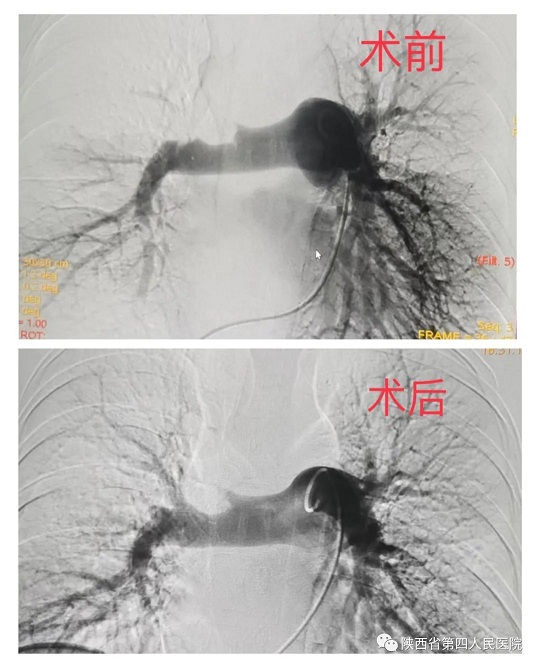

近日,21点策略指南站 心血管内科专家团队成功救治了一名突发急性肺栓塞的患者。经充分评估病情后,为患者行急诊手术,通过医护人员准确、及时的救治后,患者转危为安。患者,年轻女性,37岁,因外伤骨折术后卧床40余天,活动后出现胸闷、胸痛、气短,及一过性意识障碍,家……